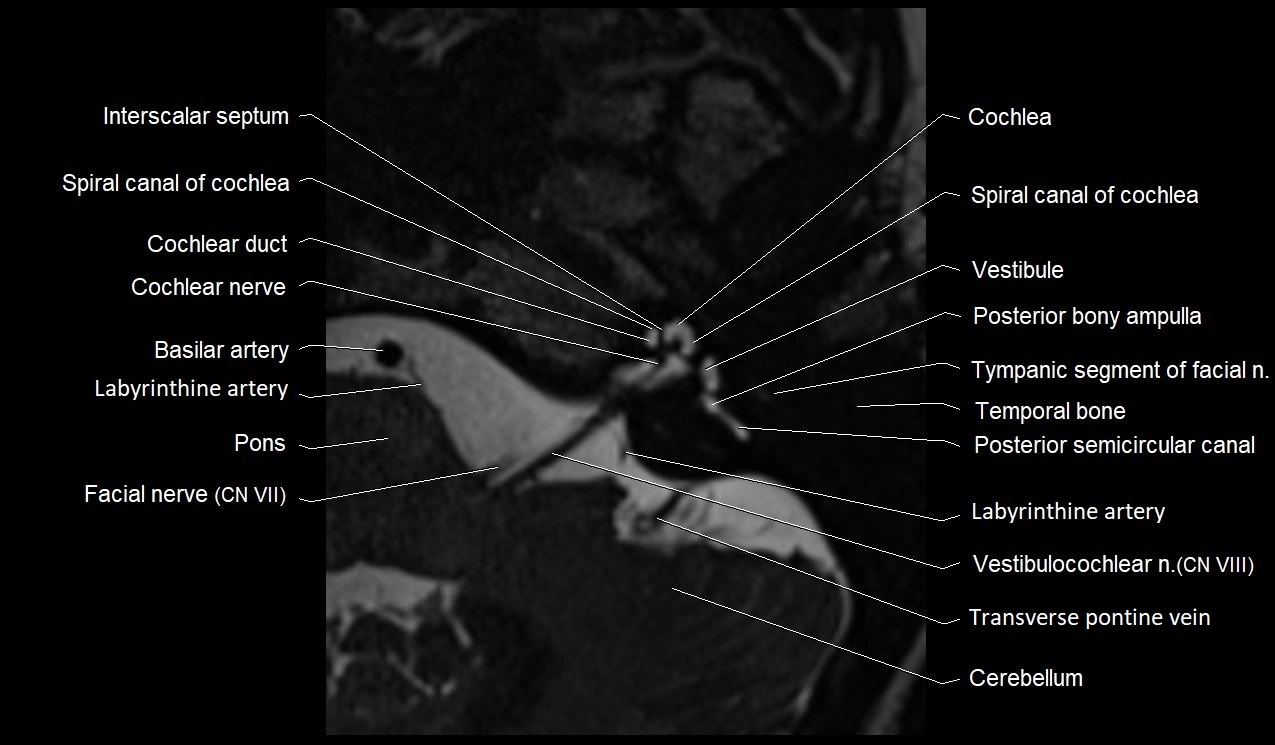

MRI Appearance

• The abducens nerve is a small, thin, linear structure

• Best visualized on high-resolution T2-weighted 3D MRI sequences (e.g., FIESTA or CISS)

• Seen as a hypointense (dark) line running from the brainstem at the pontomedullary junction, traversing the prepontine cistern, and entering Dorello’s canal under the petrosphenoidal ligament, then into the cavernous sinus, and finally the orbit

• May be challenging to visualize in standard MRI due to its small size

• Pathology may be inferred by absence, displacement, or enhancement of the nerve

MRI images

image